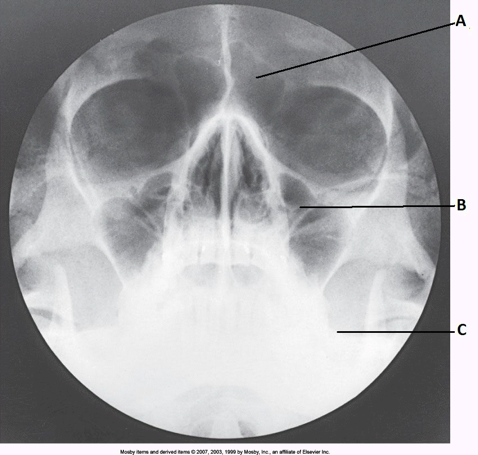

____ 84. Examine the image of the paranasal sinuses below. The letter A labels the:

a. maxillary sinuses

b. ethmoid sinuses

c. sphenoid sinuses

d. frontal sinuses

dd. frontal sinuses

a. in the lower two thirds of the maxillary sinuses

b. inferior to the floor of the maxillary sinuses

c. superior to the maxillary sinuses

d. in the middle of the maxillary sinuses

bb. inferior to the floor of the maxillary sinuses

____ 127. Which sinus is located immediately below the sella turcica?

d. glabella

bb. acanthion

____ 184. Examine the image of the paranasal sinuses below. The letter B labels the:

b. sphenoid sinuses

c. frontal sinuses

d. ethmoid sinuses

aa. maxillary sinuses